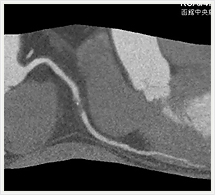

画像紹介(四肢血管治療編)

経皮的血管形成術(PTA)は先端に小さく折りたたまれたバルーンを装着したカテーテルを用いて、狭窄または閉塞してしまった血管を拡張することにより、血液の流れを確保、再開させる手技です。

この治療ではバルーンカテーテルに加えてステント(金属製のチューブ)を留置することもあります。